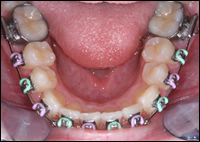

Fig 3 & 4: Upper and lower Schwartz Appliances were fabricated.